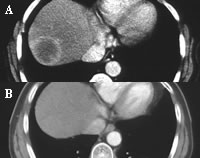

放疗是恶性肿瘤治疗的主要手段之一,但过去其对原发性肝癌的疗效不佳,主要原因是由于照射野太大而正常肝组织不能耐受肿瘤的根治剂量,使肿瘤未达致死剂量却对肝脏已经造成严重的损伤。但随着医学影像的进步,放疗技术的发展,使现代放疗在肝癌的治疗中逐渐占有一席之地。